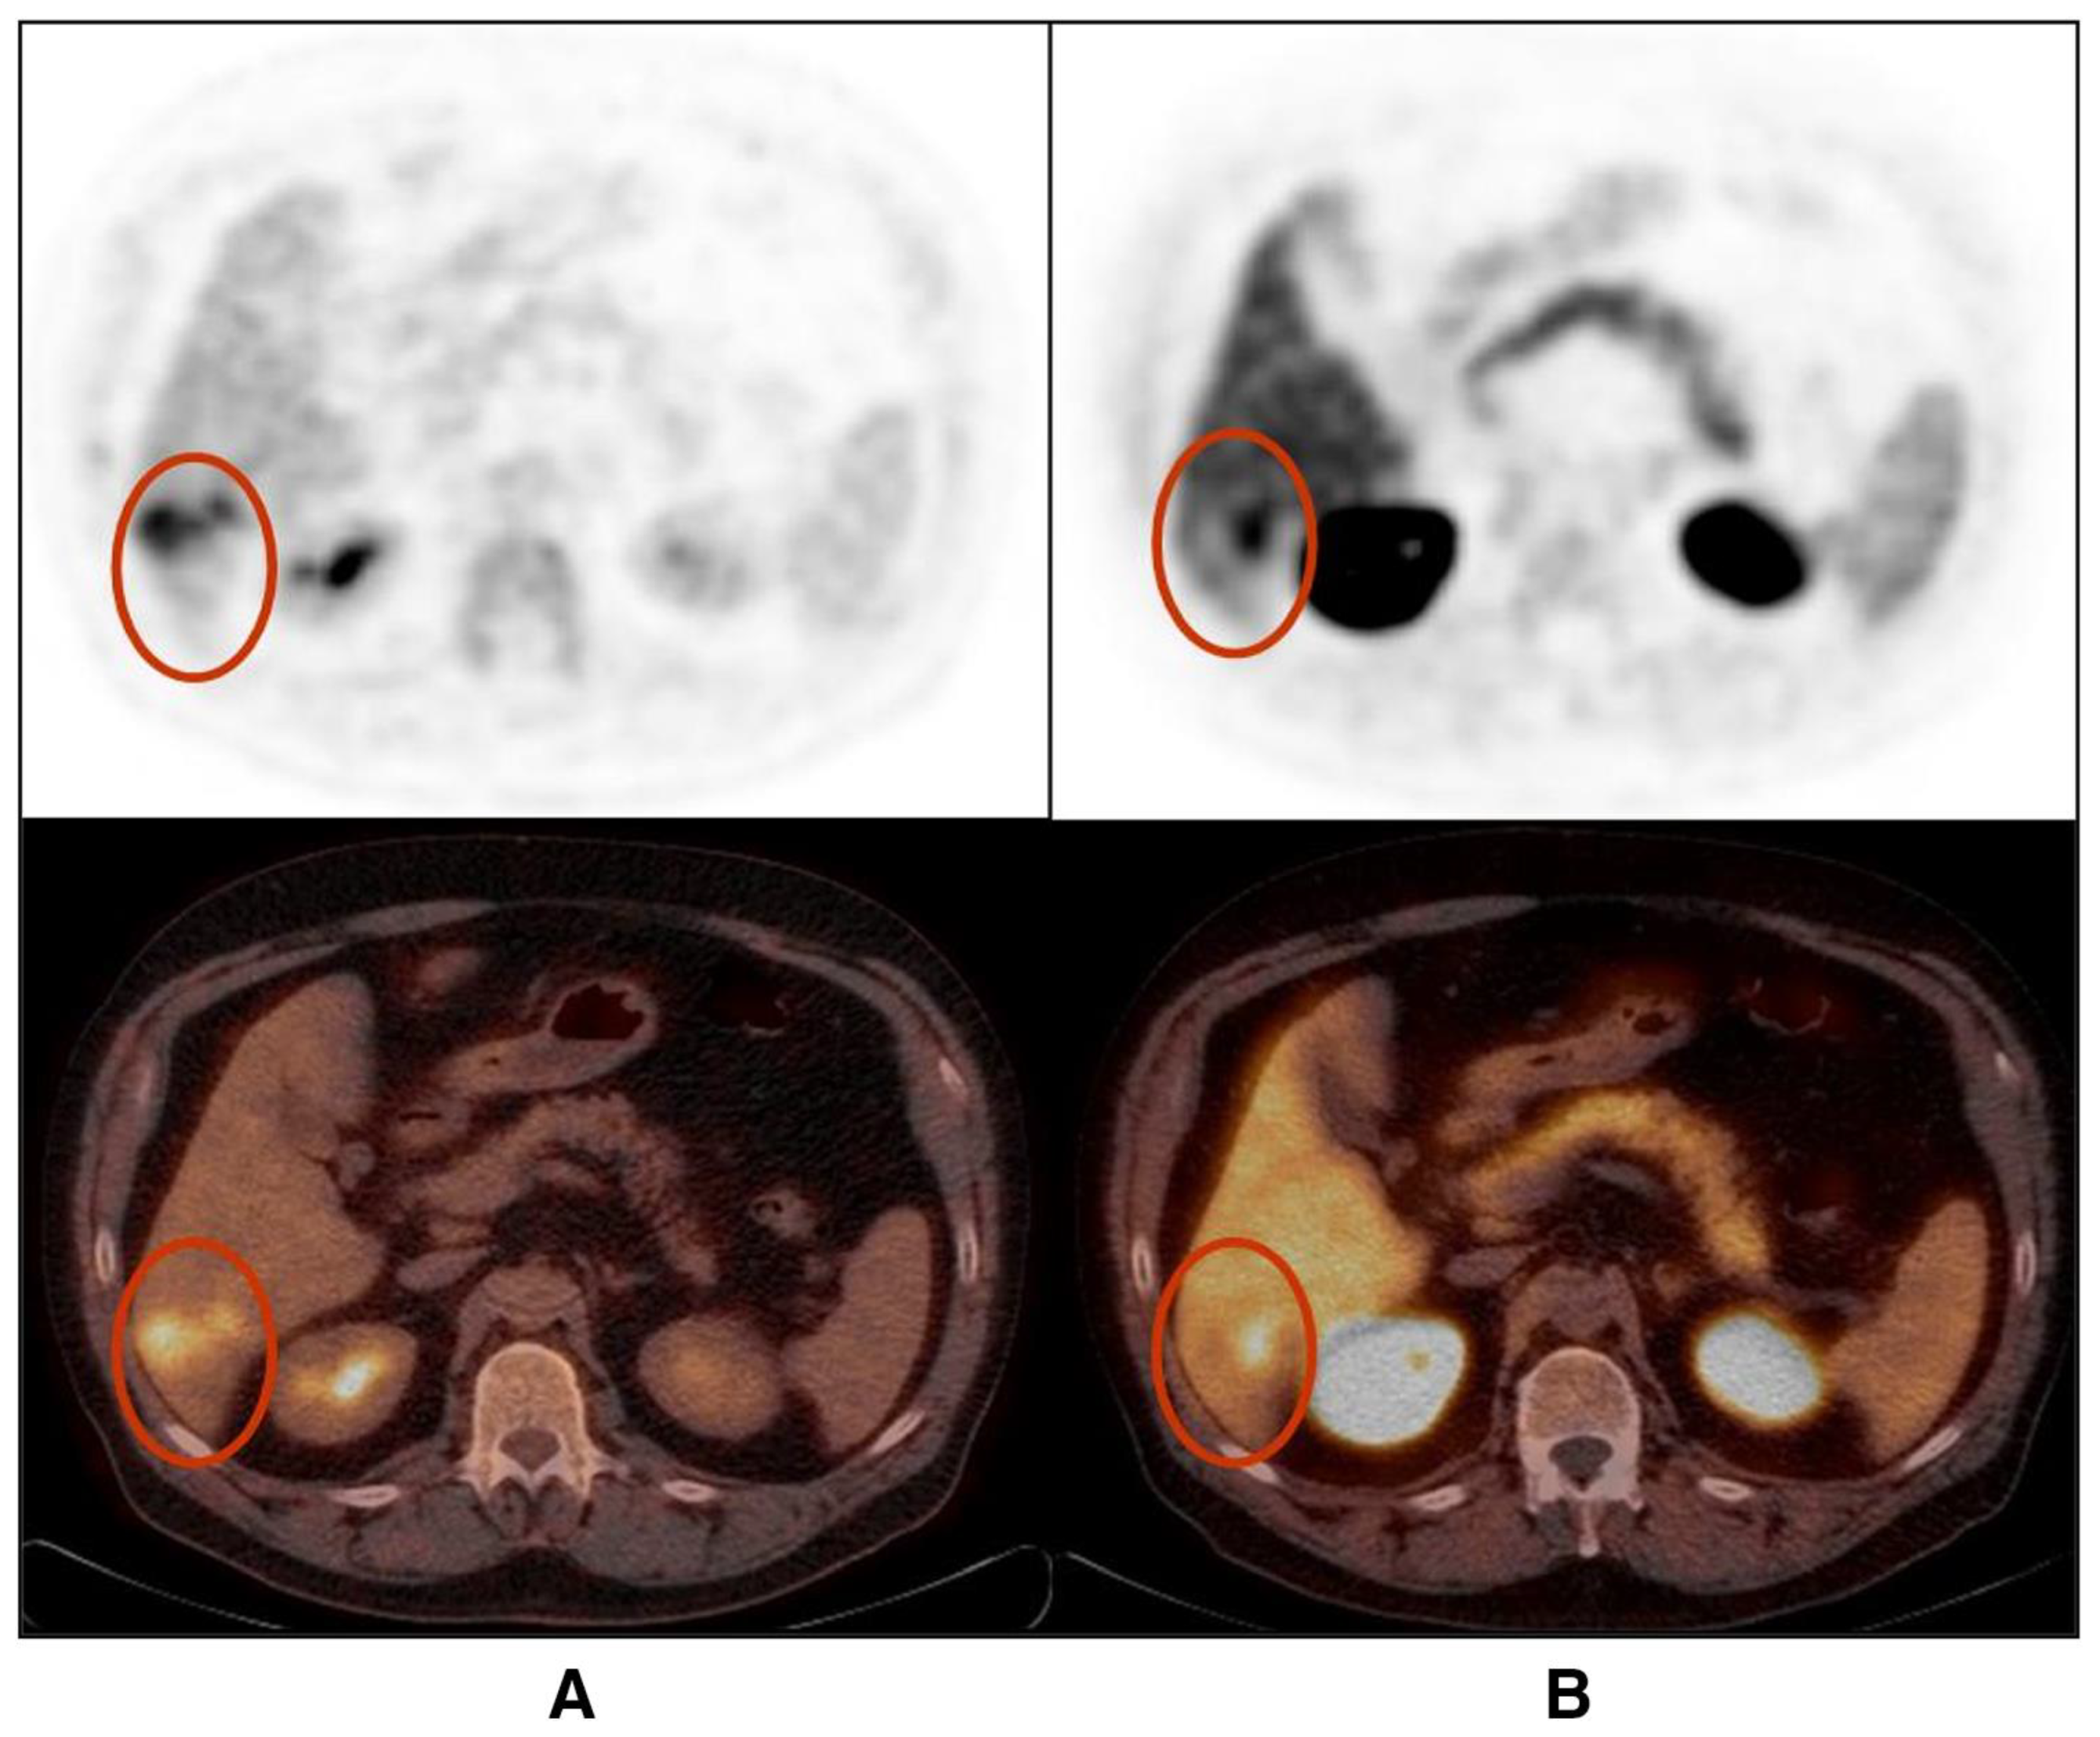

- Gündoğan, C.; Ergül, N.; Çakır, M.S.; Kılıçkesmez, Ö.; Gürsu, R.U.; Aksoy, T.; Çermik, T.F. 68Ga-PSMA PET/CT versus 18F-FDG PET/CT for imaging of hepatocellular carcinoma. Mol. Imaging Radionucl. Ther. 2021, 30, 79. [Google Scholar] [CrossRef]

- Kuyumcu, S.; Has-Simsek, D.; Iliaz, R.; Sanli, Y.; Buyukkaya, F.; Akyuz, F.; Turkmen, C. Evidence of prostate-specific membrane antigen expression in hepatocellular carcinoma using 68Ga-PSMA PET/CT. Clin. Nucl. Med. 2019, 44, 702–706. [Google Scholar] [CrossRef]